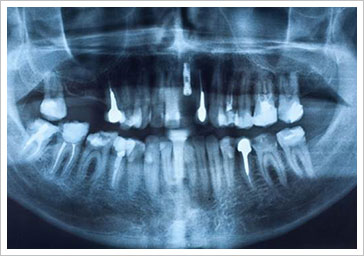

植牙完成後,每3到6個月宜回診口腔檢查,以及做人工植體周圍組織的維護。植牙後的照顧工作,應該比自然牙更謹慎,雖然植牙不會發生齲齒,但如同自然牙,也會有牙周病問題,若口腔衛生不佳,細菌很容易沿著植體到牙骨,使植體周圍骨被破壞吸收,會造成植體鬆動,甚至喪失。